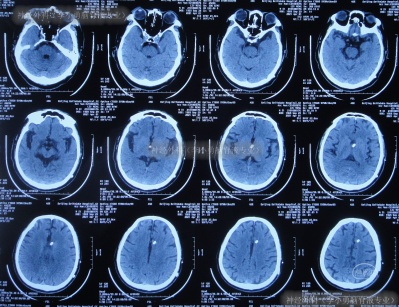

出院后3余年即2020年10月21日,第2次出现行走不稳,头晕;于是第2次就诊给予脑室腹腔分流术的医院,就诊期间出现嗜睡,查头颅CT(图-1)后给予调高分流泵压。

图-1:2020年10月21日头颅CT